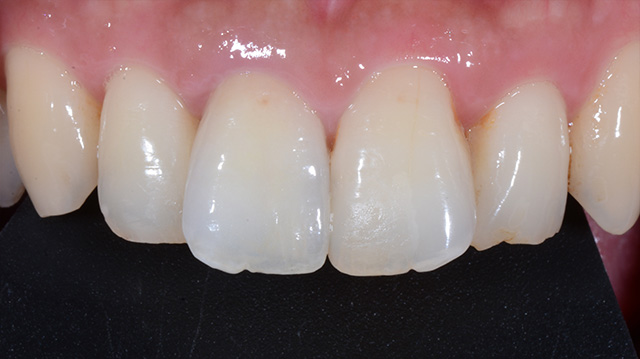

| 年代・性別 | 50代 男性 |

|---|---|

| 主訴 | 前歯を綺麗にしたい |

| 治療回数 | 3回 |

| 治療期間 | 約1ヶ月 |

| 費用 | 仮歯 5,500円 ジルコニアクラウン 176,000円 |